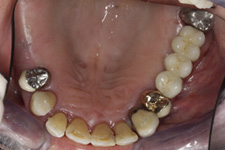

V případě chybění většího počtu zubů v postranních úsecích čelistí je možné ošetření pomocí implantátů, které nahradí ošetření pomocí snímacích náhrad kotvených na zbývajících zubech nebo patře.

Podmínkou je opět dostatečné množství kosti.

Protetické řešení může být pomocí můstku, který je kotvený na implantátech nebo pomocí jednotlivých korunek na implantátech.

V zásadě je možné do těchto můstků zařadit i přirozené zuby, zejména pokud je potřeba tyto zuby ošetřit proteticky – korunkami. Korunky nebo můstky mohou být na implantáty nacementovány nebo přišroubovány.

Zdravé zuby zůstanou zachovány a přitom náhrady jsou pevné, jako na vlastních zubech